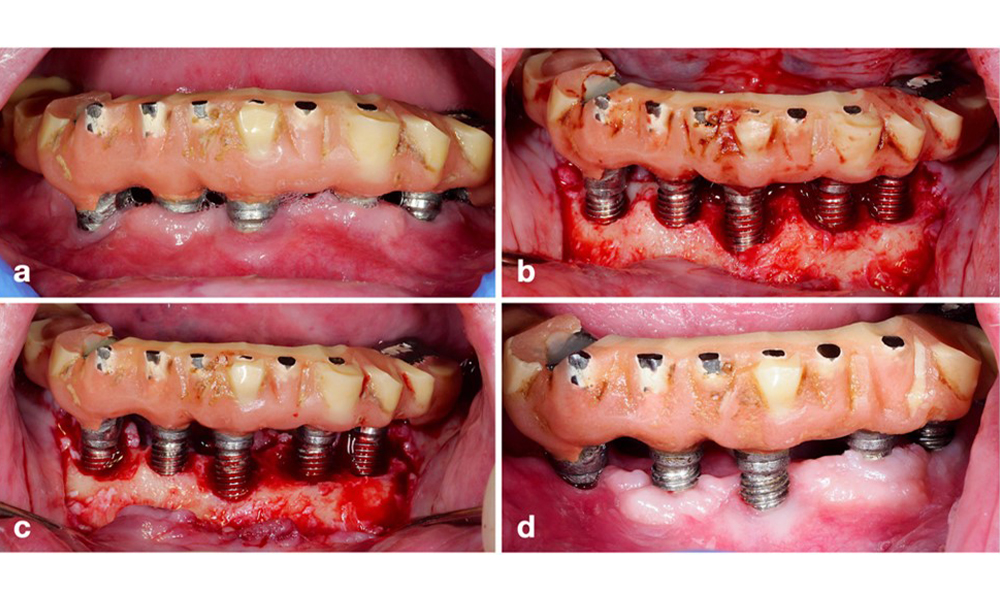

La restauration prothétique doit être retirée pendant le traitement non chirurgical et chirurgical afin d'améliorer l'accès à la surface de l'implant. Le choix de l'intervention chirurgicale (résective, reconstructive ou combinée) dépend de plusieurs facteurs : (1) la morphologie du défaut (par exemple, horizontal, déhiscence, intra-osseux ou combiné) (figure 10), (2) la surface de l'implant (c'est-à-dire, tournée ou modifiée/"rugueuse"), et (3) la présence ou l'absence d'une muqueuse kératinisée et attachée suffisante.

Une approche résective (c'est-à-dire une gingivectomie et/ou un lambeau positionné apicalement, avec ou sans remodelage osseux) doit être choisie dans les cas de perte osseuse principalement horizontale ou de défauts larges, où le potentiel de régénération osseuse est limité (figure 11).

Pour les implants dont la surface est modifiée et dans les régions où la régénération osseuse est improbable, l'implantoplastie doit être envisagée. Cette procédure consiste à retirer les fils de l'implant et à lisser la surface micro-structurée de l'implant à l'aide d'instruments rotatifs (figure 12). Cette approche facilite la décontamination complète de la surface de l'implant et, surtout, améliore le contrôle du biofilm postopératoire (Bertl et Stavropoulus 2021 ; El Chaar et al. 2020 ; Geremias et al. 2017). Faute de preuves cliniques suffisantes, le rôle de l'implantoplastie est controversé (Herrera et al. 2023 ; Ramanauskaite et al. 2021), mais les craintes concernant l'induction d'une inflammation par le dépôt inévitable de particules de titane et le risque accru de fracture de l'implant en raison de la réduction de sa résistance n'ont pas été étayées (Stavropoulos et al. 2019).